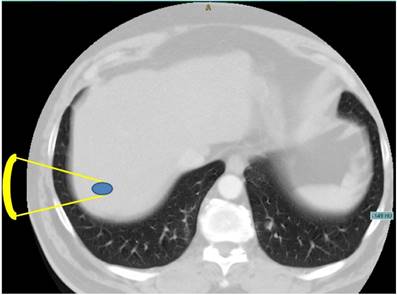

As an alternative, High Intensity Focused Ultrasound (HIFU) represents a completely non-invasive modality for local thermal tumour ablation without damaging the surrounding parenchymal tissue [8]. Several patient studies have investigated the feasibility of HIFU for the treatment of liver tumours or metastases [9,10,11], showing a strong therapeutic response to cancer tissue with almost negligible side effects. However, the tumour position affects its ability to be treated, for instance the location in the hepatic dome directly below the diaphragm [12,10]. The convex area of the liver is adjacent to the air filled lung representing an invincible border for diagnostic and therapeutic ultrasound [13]. As demonstrated in Figure 1, the shortest acoustic pathway transthoracically through the lung into the liver dome is currently impossible.

Figure 1

Axial CT image of the upper abdomen demonstrating the problem of a direct transpulmonary access to the liver. Shortest projection from a hypothetical extracostal transducer placement is indicated (yellow lines).